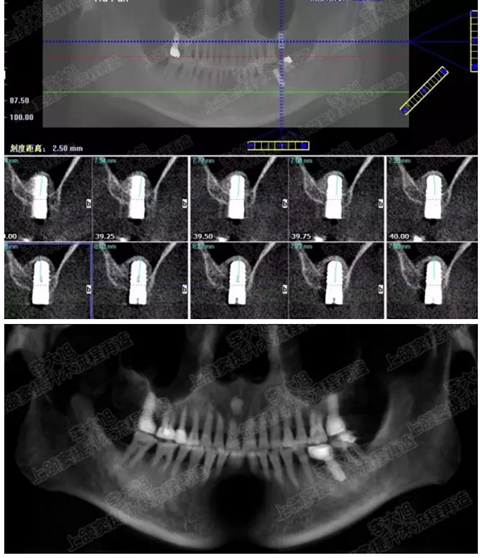

病例二

剩余骨量2mm

003.png

提升10mm

004.png